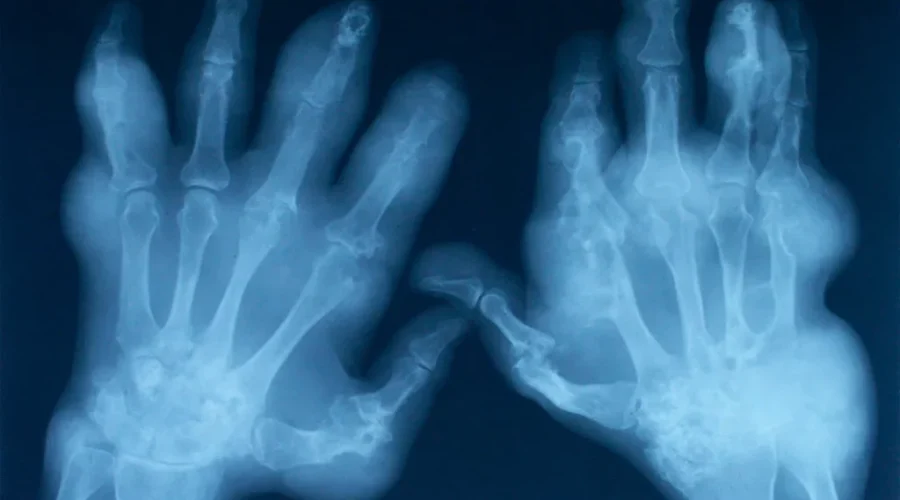

More and more patients are being referred for hip and joint replacement surgery, due to a an aging population.